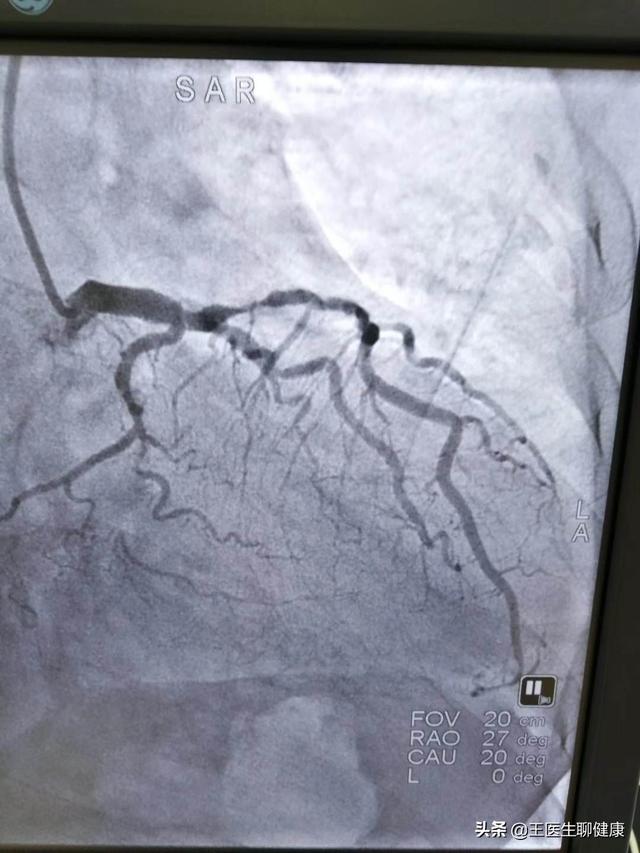

4、Les lésions multi-branches avec calcification : les résultats de la coronarographie montrent des lésions multi-branches dans les artères coronaires, y compris le tronc principal gauche + les lésions à trois branches, qui peuvent être traitées par la pose d'un stent, mais il faut implanter de nombreux stents, et les lésions calcifiées sont plus difficiles à opérer, avec une longue durée d'opération et une grande quantité de rayons. Les patients peuvent également envisager un pontage chirurgical, mais la récupération est lente et le traitement long. En fonction des circonstances, le médecin proposera un plan idéal.

La figure ci-dessous montre une lésion multi-branches du tronc principal gauche.